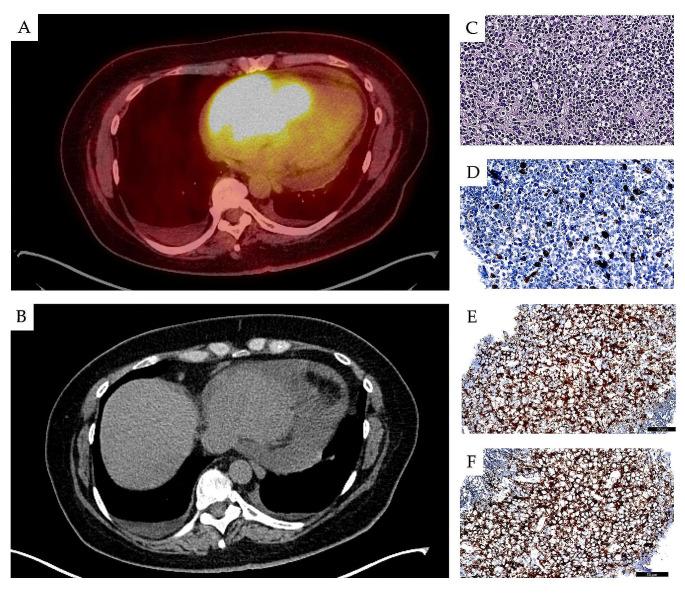

Chronic lymphocytic leukemia/small lymphocytic lymphoma (CLL/SLL) is a common leukemia characterized by clonal expansion of mature CD5+/CD23 + B cells in the blood, bone marrow (BM) and lymphoid tissues. CLL can undergo extramedullary and extranodal infiltration, with one study noting an incidence of only 0.3 per 100,000 people, and in 17.6% of CLL patients in another report. The most common extranodal sites of leukemic involvement are the skin and central nervous system; however, other organs, including liver, lungs, kidney, gastrointestinal tract, bone, prostate and heart, are occasionally involved. The prognostic significance of extra-medullary CLL is still under debate, but the prognosis in such patients seems to be better in the era of novel targeted drugs. Following a diagnosis of extranodal CLL, survival appears to depend on the site of infiltration. This review presents an overview of CLL in patients with extramedullary and extranodal leukemic lesions, focusing on its epidemiology, pathogenesis, prognosis, clinical characteristics and treatment results.